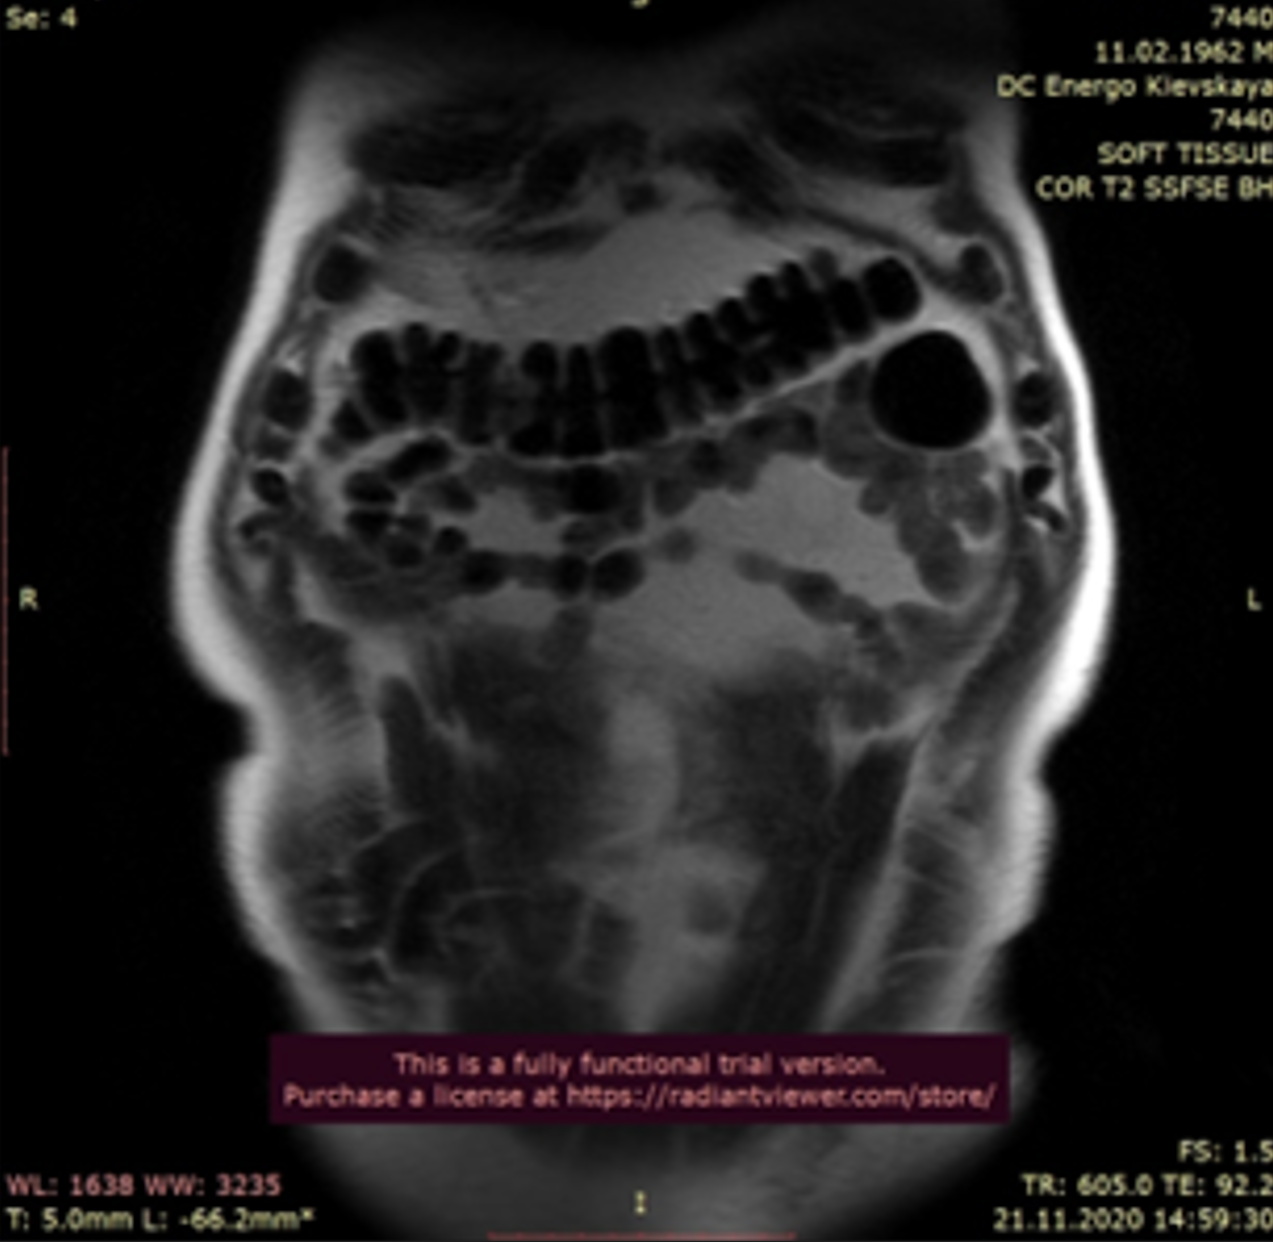

При МРТ (рис.1, 2) брюшной полости под селезеночным изгибом толстой кишки выявляется образование 5 см в диаметре с тонкой равномерной стенкой, горизонтальным уровнем жидкости, сообщающееся с просветом кишки. Визуализируемый участок паретически изменен. Данный участок не изменялся в течение всего исследования. В связи с чем заподозрены: дивертикул тощей кишки (?), инородное тело (?), опухоль (?).

Рис. 2. / Fig. 2.